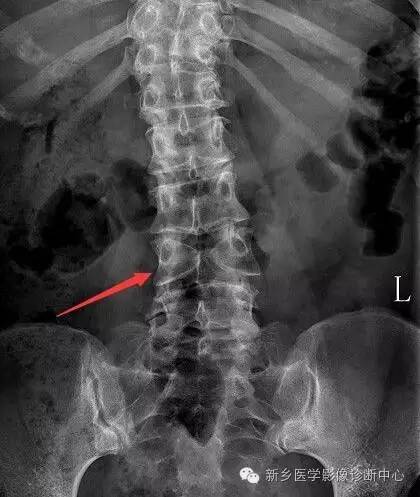

半椎体:椎体的一半缺如或发育不全,半椎体较正常椎体小,圆形、椭圆形、楔形,位于中线一侧;胸椎半椎体多合并有并肋畸形

脊椎椎体畸形(半椎体、蝴蝶椎)